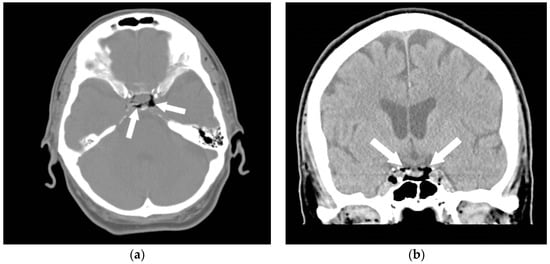

5. Air Embolism Management

5.2. Advanced Management

5.3. Air Aspiration